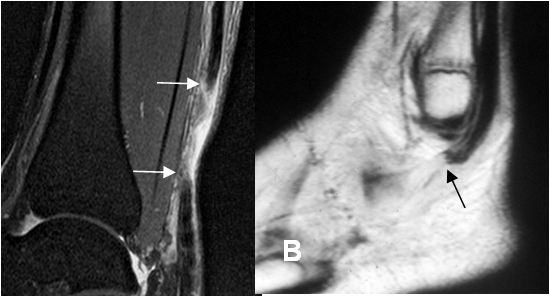

Fig 77 B. Ruptura tendinosa completa.

A: RM sagital en STIR. Ruptura completa del aquiles, con líquido y tejido de granulación entre los extremos.

B: RM sagital en T1. Ruptura de los tendones peroneos, los cuales están retraídos y con extremos a nivel del maleolo externo.